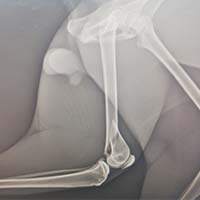

Yalıkavak veteriner kliniğimizde gerçekleştirdiğimiz ortopedik cerrahi uygulamalar:

Ortopedik cerrahi oldukça titizlik ve özen gerektiren cerrahi uygulamalardır. Diğer cerrahi disiplinlere nazaran asepsi ve antisepsi (sterilizasyon) konusunda ASLA hata kabul etmez. Eğer bu aşamada özensiz davranılırsa, postoperatif süreçte kemik dokunun iltihaplanmasına neden olup, kemiklerin kaynaması gecikmiş olur.